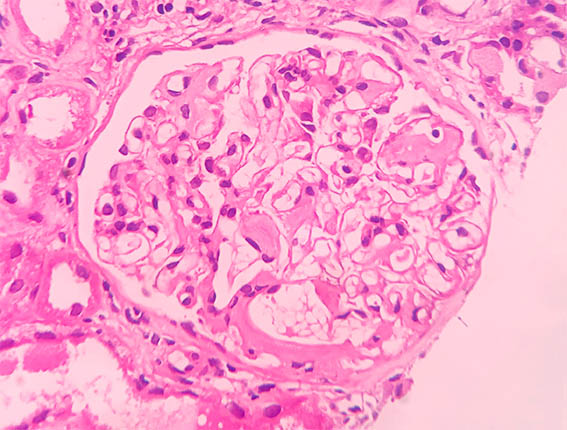

Figure 3.

H&E, X400.